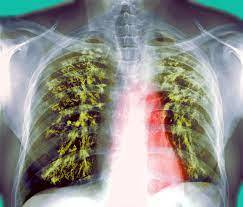

در سراسر جهان، سل سالانه حدود ۱.۶ میلیون نفر را می‌کشد. هنگامی که فرد مبتلا به سل عطسه یا سرفه می‌کند، از طریق قطرات پخش می‌شود و سل به ریه‌ها و گاهی دیگر اندام‌ها حمله می‌کند.